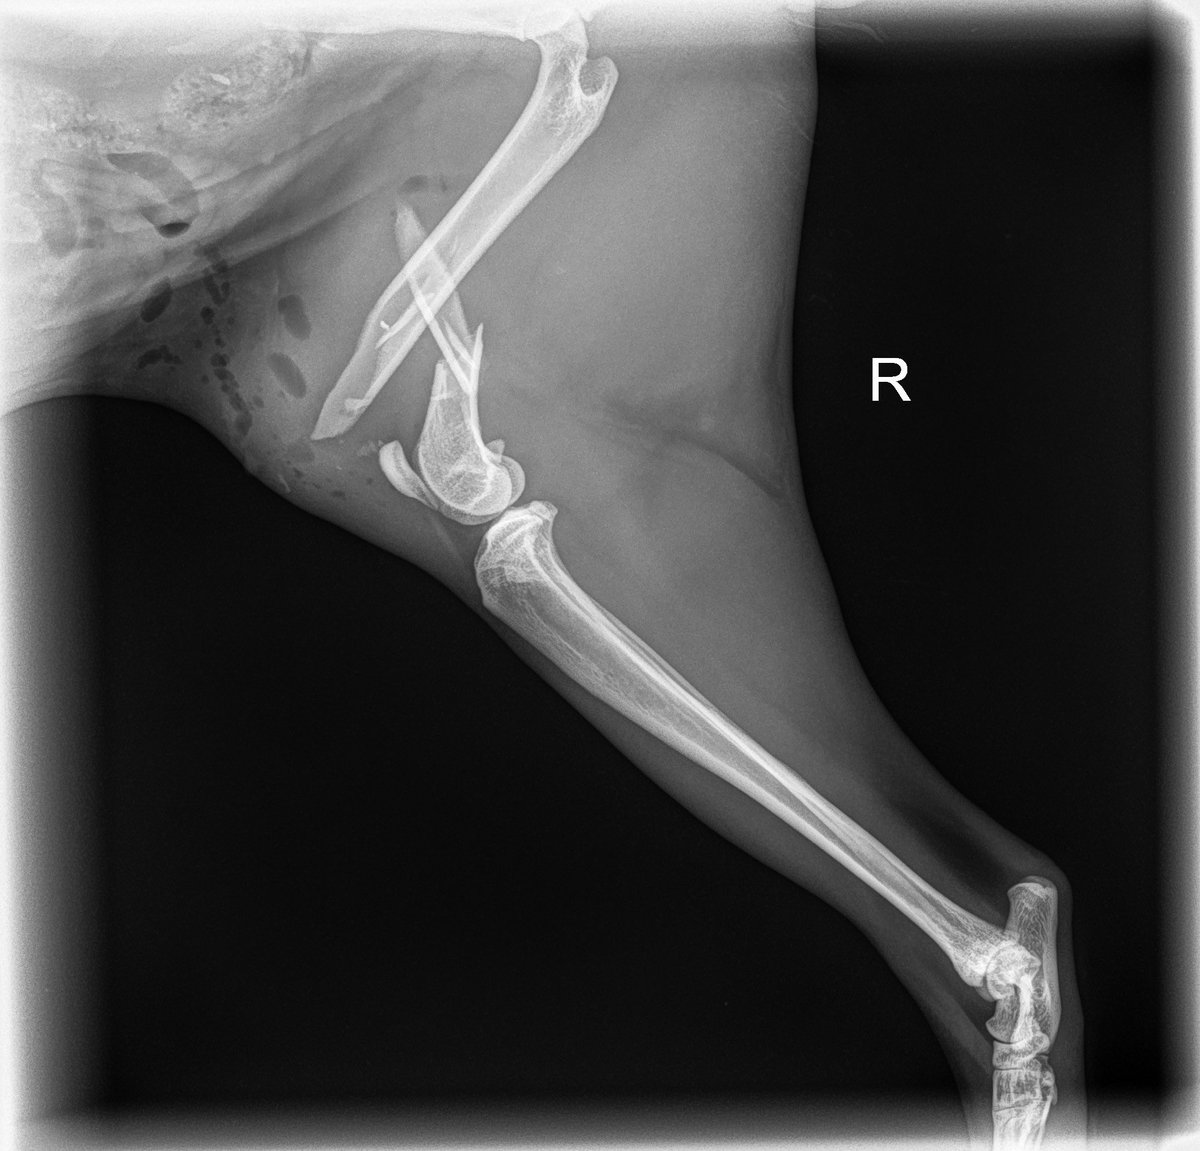

ouch 😭 poor baby's femur is very broken. He needs surgery, maybe amputation, will be calling surgeons in the morning to try to get him in somewhere asap. Thank you so much to everyone who has donated, you are all so amazing and kind 🩷